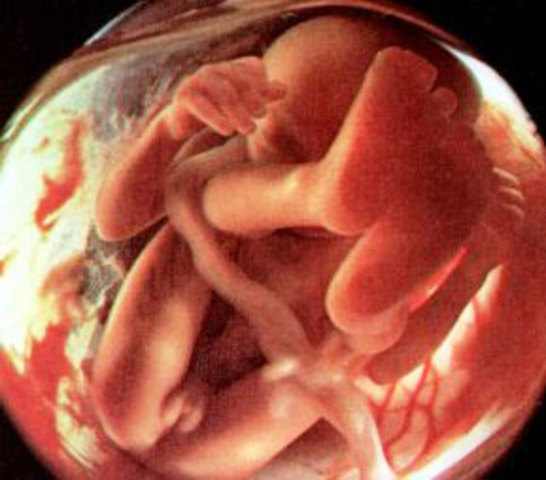

El esqueleto, hasta ahora constituido únicamente de cartílago, acoge ahora las primeras células óseas. Los huesos de los brazos y de las piernas se solidifican y se alargan, al igual que las costillas y la pelvis. Las columna vertebral se desarrolla y los músculos y los tendones permiten ya algunos movimientos.

La cabeza representa todavía aproximadamente una tercera parte del cuerpo. El embrión mide ahora más de 8 cm y pesa casi 30 g.